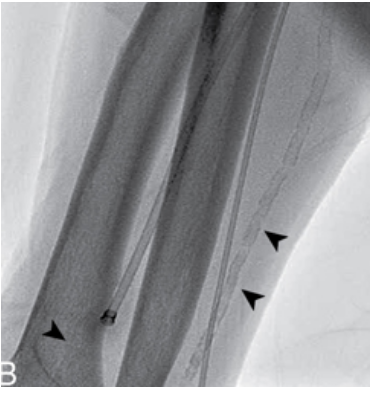

what are these arrows pointing at

Calcification